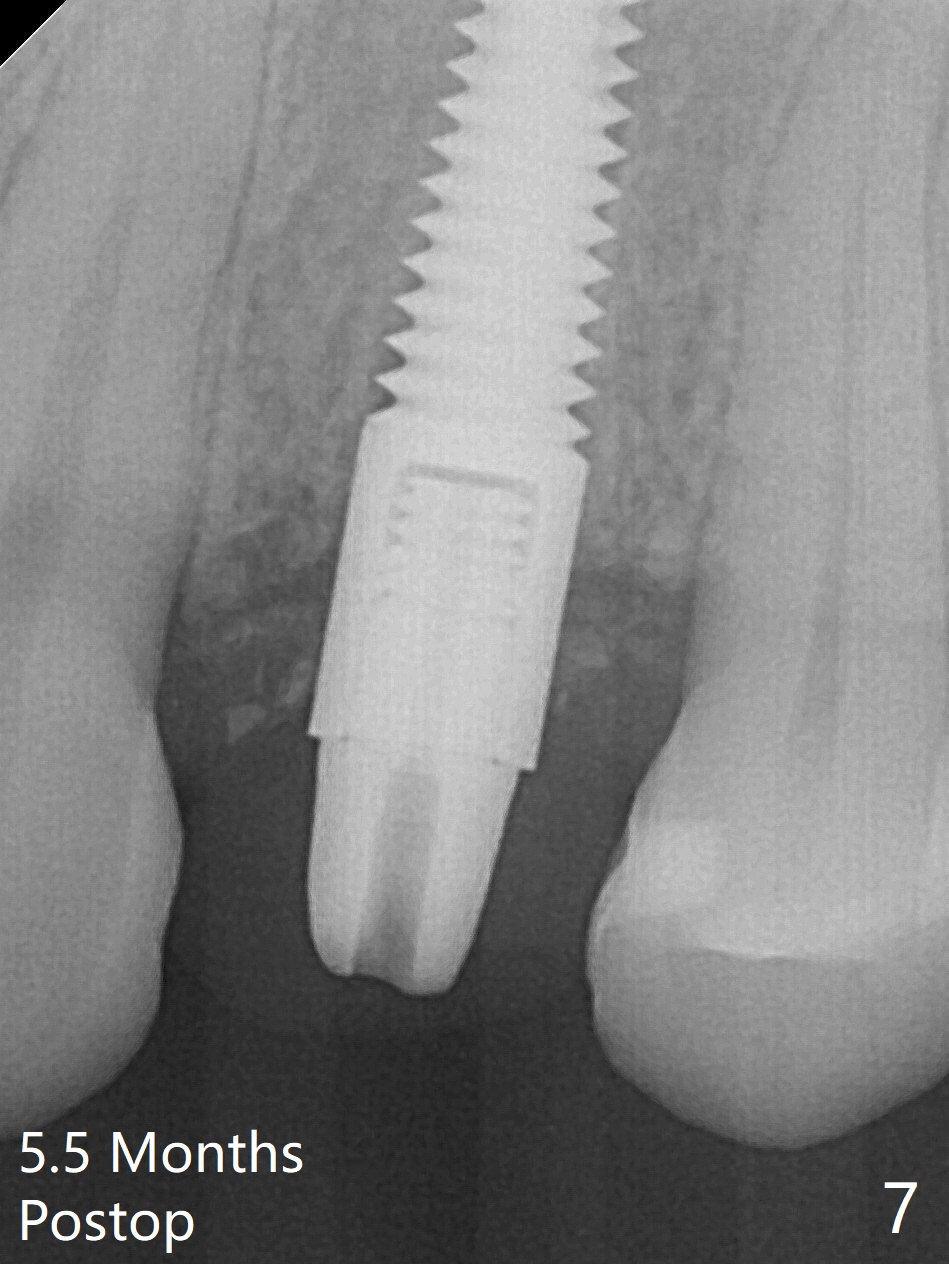

Since there is no buccal plate atrophy at 4, or 8, socket shield is not attempted at #31. Extraction turns out to be difficult because of tooth fracture. The buccal and palatal flaps have to be elevated minimally for tooth sectioning and purchase point formation. More surprising, a 4.5 mm implant appears to be too wide for the space; a 4x17 mm implant achieves insertion torque >60 Ncm (Fig.1,2). In fact Vanilla graft is placed before and after implantation. The advantage of bone graft before implant is that the graft is able to be placed as apical as possible to repair the apical defect if it is present. The disadvantage is hemorrhage. After placement of a 3.5x5 mm abutment, an immediate provisional is fabricated (Fig.3 P), which seems to be able to hold the separated buccal papillae in place. The latter heal around the immediate provisional 9 days postop (Fig.4). Because of the seal, the bone graft remains in place 1 month postop (Fig.5). There is no bone loss 5.5 months postop (Fig.6,7) or 6.5 months postop (immediately post cementation, Fig.8).